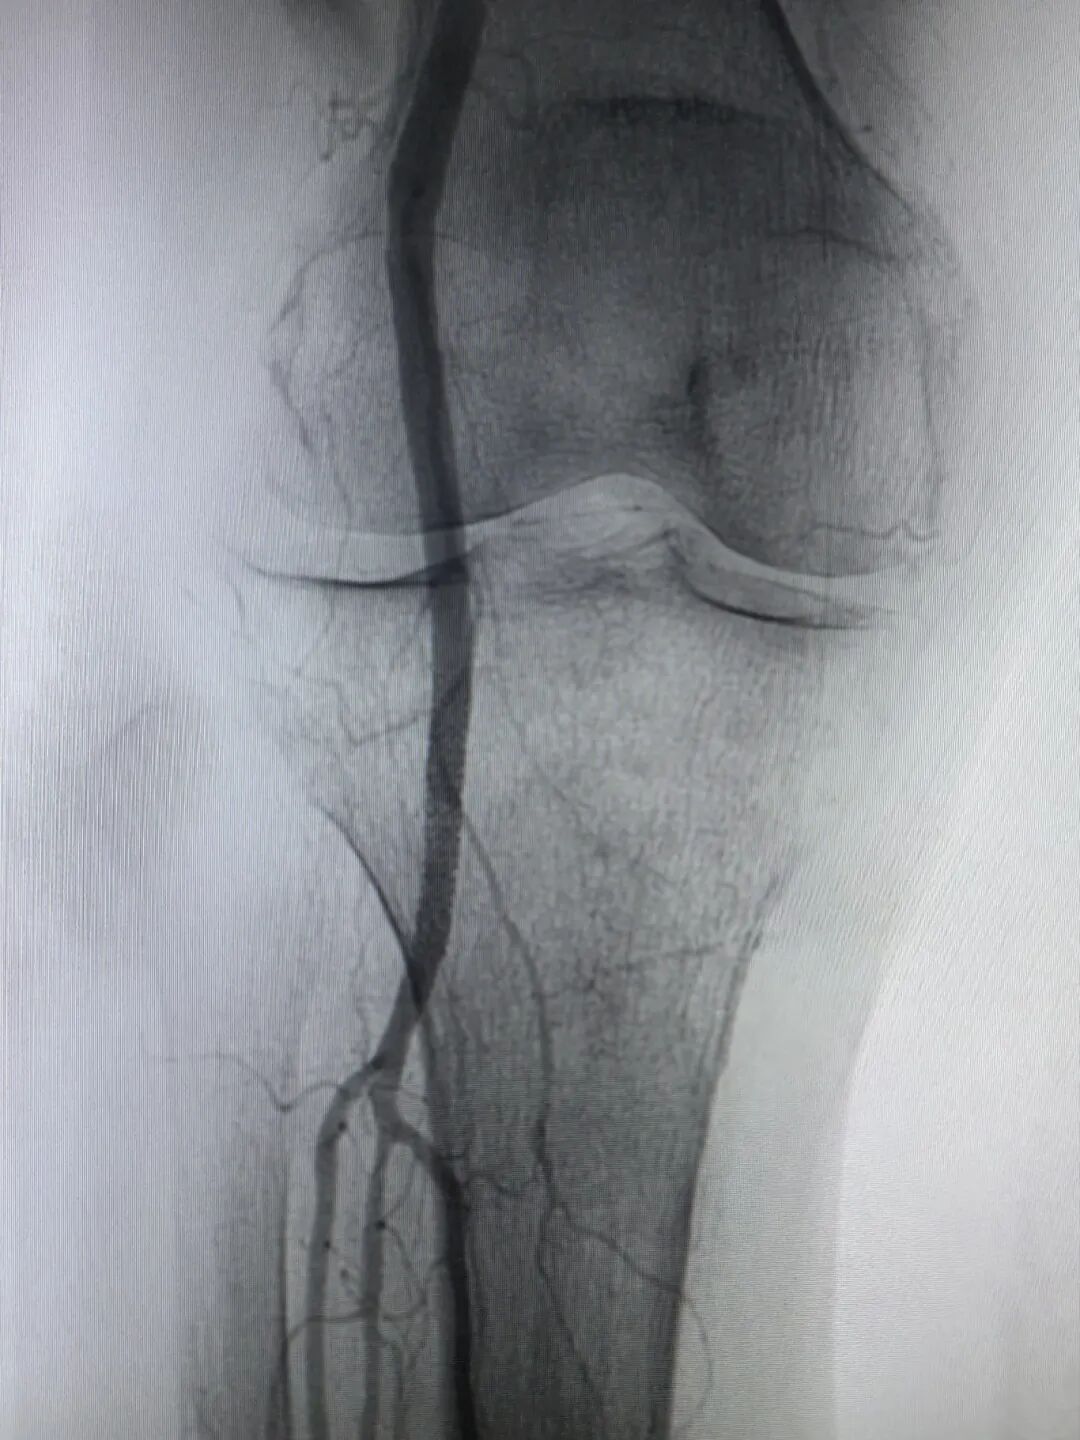

a0a1e537118f198eda9331c83e1efd2a.jpeg 5a665816715e62930adbc5c389d5b167.jpeg

(介入术后闭塞的血管完全再通)

两个小时后,手术顺利完成。孙奶奶右下肢的皮温、皮色即刻改善,足背动脉搏动恢复,疼痛麻木消失。从入院到血运重建,全程高效顺畅,没有浪费一分一秒。